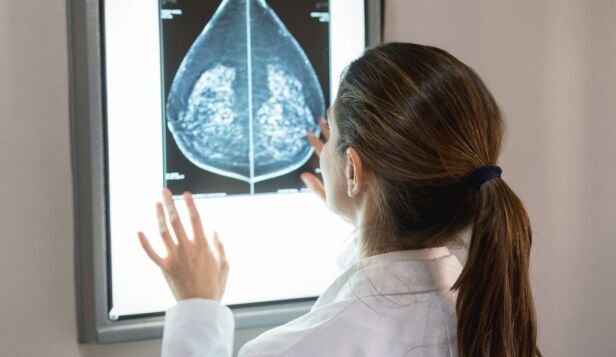

BCRF researcher Dr. Wendie Berg outlines what happened to breast screening in the early days of the pandemic—and what is safe now

As the pandemic has stretched on for more than half a year, many women are undoubtedly wondering: Should I go in for my annual mammogram? Is it safe?

Back in March, in the early weeks of the pandemic as emergency rooms were filling with COVID-19 patients and states were starting to issue shelter-in-place orders, women found out their annual breast cancer screenings were canceled or postponed. Experts and consortia issued guidelines indicating it was safe to hold off on a screening mammogram for a couple of months.

As “a couple of months” has turned into a new normal, recommendations on breast cancer screening have continued to evolve. Recent research indicated a significant decline in breast cancer diagnoses (by as much as 51.8 percent) in the U.S. from March 1 to April 18, causing some experts, including BCRF’s Founding Scientific Director Dr. Larry Norton, to warn of a coming flood of diagnoses, potentially at more advanced stages. BCRF asked Dr. Wendie Berg for a “state of the mammogram” in the time of COVID-19.

In short: It’s safe to get your mammogram now, and if yours was postponed, reschedule it now. Read on for more.

What happened with breast cancer screening at the start of the COVID-19 pandemic, and where are we at now?

At the start of the pandemic, we needed to implement new policies and practices in facilities to make them safe. We are up close and personal when we’re doing breast imaging. But in mid-March, we didn’t have enough masks for our technologists. Our facility closed to screening from March 20 to April 24. Some places were longer than that. Others didn’t stop. But there was a big pause at that time.

Obviously, at that time, too, there was concern about overwhelming the health care system. There were at least a couple months where most patients had their surgeries delayed, but doctors were still treating their cancer and keeping it from spreading through endocrine therapy and/or chemotherapy. Most facilities never stopped seeing patients with symptoms. But what really did stop was routine screening.

When our facility closed, we revisited policies and practices and changed our waiting rooms so that patients could be socially distant from others, and we put extensive cleaning protocols in place. Now, most importantly, we have enough masks. Many facilities are also, for example, registering patients in the car or out front, so they don’t come into the building until they need to, and screening for exposure and taking temperatures. At this point, facilities have really made the changes that are needed to be safe. Even as there are COVID-19 spikes, I can’t foresee breast imaging facilities closing down again like before, because they’ve adapted. It’s safe to get your mammogram.